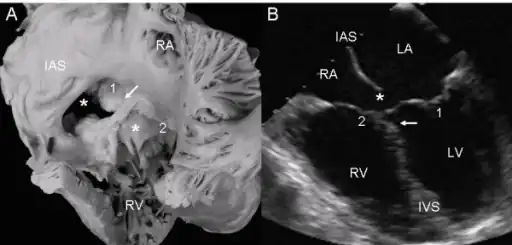

a,b)Atrioventricular septal defect with two separate atrioventricular valves.

Ultrasound showing a complete atrioventricular septal defect

A variety of different classifications have been used, but the defects are usefully divided into "partial" and "complete" forms.

- In the partial AVSD, there is a defect in the primum or inferior part of the atrial septum but no direct intraventricular communication (ostium primum defect).

- In the complete AVSD (CAVSD), there is a large ventricular component beneath either or both the superior or inferior bridging leaflets of the AV valve. The defect involves the whole area of the junction of the upper and lower chambers of the heart, i.e. where the atria join the ventricles. There is a large hole between the lower portion of the atria and the upper or 'inlet' portion of the ventricles and this is associated with a significant abnormality of the valves separating the atria from the ventricles. The valves in effect become a common atrio-ventricular valve, and the severity of the defect depends largely on the supporting attachments of the valve to the ventricles and whether the valve allows dominant flow from the right atrium to right ventricle and from left atrium to left ventricle ("unbalanced" flow). The overall problems are similar to those of VSD but are more complicated. There is an increased flow of blood to the lungs through both the ventricular and atrial components of the defect. In addition, the abnormal atrio-ventricular valve invariably leaks, so that when the ventricles contract, blood flows not only forwards to the body and the lungs, but also backwards into the atria. The back-pressure effect on the atria causes congestion of blood in the left atrium in particular, and this in turn causes congestion in the veins draining the lungs. The effect on the baby is to worsen the heart failure that is associated with an isolated VSD and to hasten the onset of pulmonary hypertension. It should be mentioned that CAVSD is found in approximately one-third of babies who have Down syndrome, but it also occurs as an isolated abnormality.